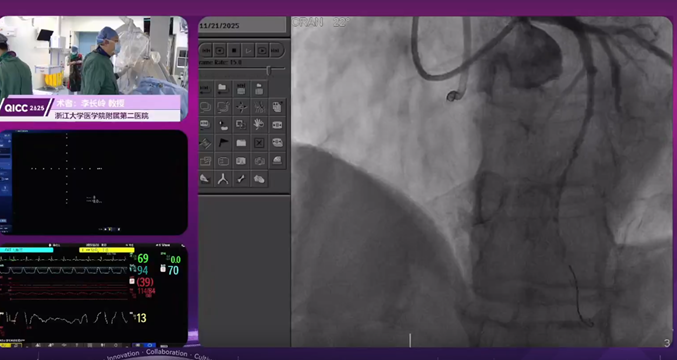

攻坚迂曲钙化:旋磨联合冲击波治疗前降支复杂病变

毛晓波教授演示的病例为前降支复杂病变,造影提示血管重度扭曲伴弥漫性钙化,远端血管闭塞且远端心尖段累及钙化病变。术中初始微导管尝试通过病变段受阻,更换适配指引导管后顺利抵达目标区域。鉴于病变钙化负荷重且血管走行迂曲,术者选用微创®冠脉的FireRaptor®冠脉旋磨系统旋磨导丝,首次采用1.25mm旋磨头,以10万转/分钟的转速启动旋磨治疗。毛晓波教授分享了复杂钙化病变的旋磨实操心得:操作需遵循 “缓慢推进、分段旋磨” 原则,让磨头和病变充分接触;术中持续通过造影动态评估血流状态,重点监测有无慢血流或无复流发生;若出现血流异常,需及时停止旋磨,通过交换微导管并给予措施优化血流后再继续操作。经旋磨预处理充分改善血管钙化形态、降低血管阻力后,后续采用3.5mm冲击波球囊进一步处理深部钙化,最终造影提示血管血流恢复通畅。